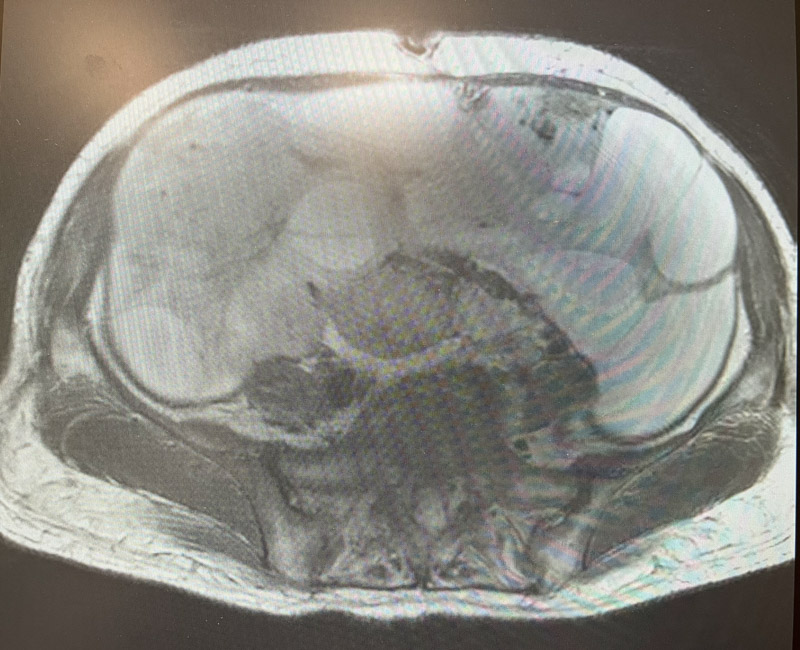

婦科二病區(qū)主任陳煜岊認(rèn)真詢問(wèn)病史,并為患者進(jìn)行專科檢查。B超提示于盆腹腔見(jiàn)一186mm×117mm巨大囊實(shí)性腫物,上至劍突下,右至腋前線,左至腋中線。

由于患者已出現(xiàn)腹脹痛、進(jìn)食差、心慌等壓迫癥狀,而且不能排除腫物是惡性腫瘤的可能,如不及時(shí)手術(shù),腫物進(jìn)一步增大,可能出現(xiàn)腫物破裂、感染、惡性腫瘤轉(zhuǎn)移等情況。

經(jīng)過(guò)詳盡周密的術(shù)前評(píng)估及準(zhǔn)備,在麻醉科的仔細(xì)的監(jiān)護(hù)下,婦科手術(shù)團(tuán)隊(duì)開(kāi)始進(jìn)行手術(shù),雖然已有心理準(zhǔn)備,但看到腹腔內(nèi)的巨大腫物還是讓所有人感到震驚。手術(shù)過(guò)程中,進(jìn)行的每一步都如履薄冰,手術(shù)醫(yī)生憑借其精湛的技術(shù)以及對(duì)盆腔復(fù)雜解剖結(jié)構(gòu)的精準(zhǔn)把控,抽絲剝繭,一寸一寸推進(jìn),最終將巨大囊實(shí)性腫物取出體外,幫患者拆除了“炸彈”。